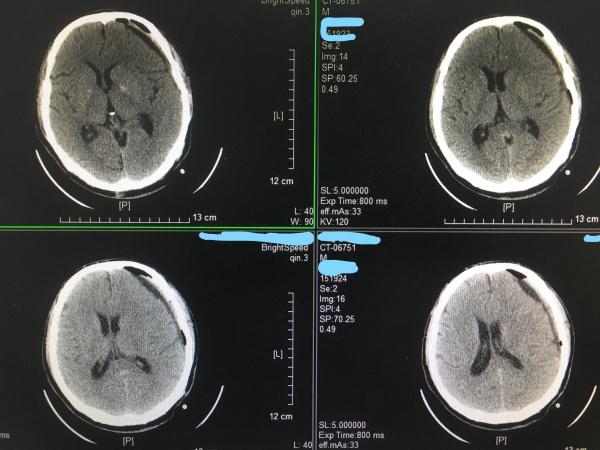

患者老年男性,因右侧肢体乏力2天***,行头颅CT检查如下:

片中可见左额颞顶部大量硬膜下血肿,中线明确右移,我们仔细阅片,发现有两处可疑分隔,所以想着预约个MRI看仔细点,但MRI又不能急诊,所以还是直接手术了,术前向家属告知分隔之可能,必要时可行两根血肿穿刺针引流或软通道引流。

手术过程还是很顺利,引流通畅,术后复查CT:

可见脑组织明显复位,血肿大部分引流,观察穿刺针深度及侧孔情况,予以拔出3mm-5mm左右,一天后拔除血肿穿刺针。